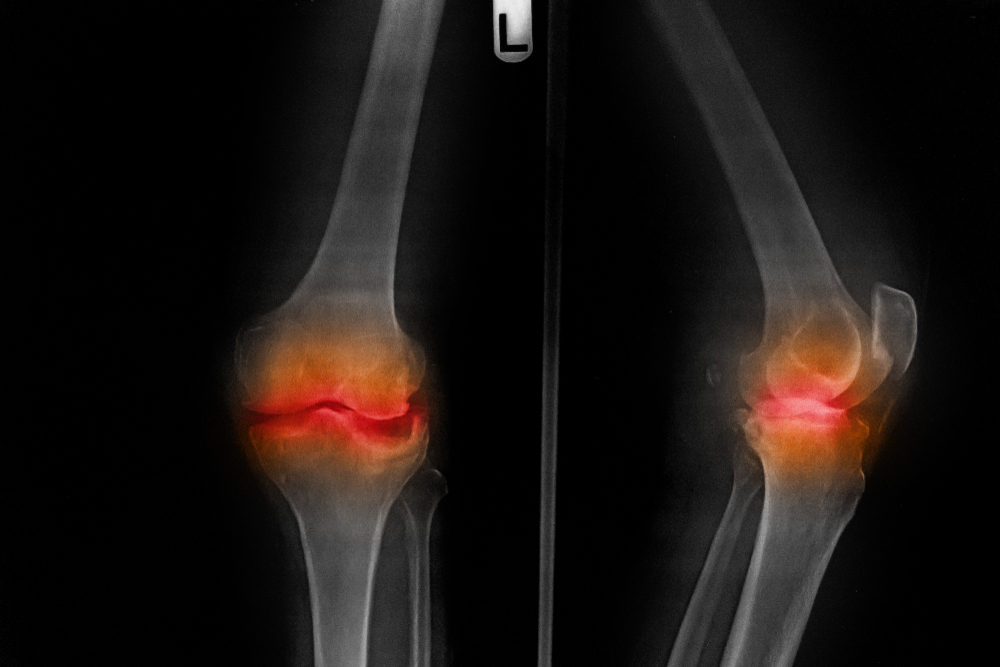

Why Does My Knee Hurt A Lot?

advice, injury, knee

injury, knee

How Long Does It Take To Treat Knee Pain?